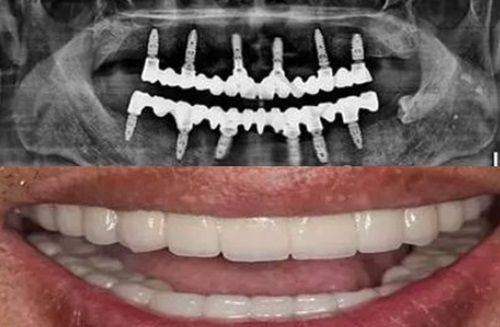

例如,数字化口腔影像系统可以清晰显示患者的口腔状况,帮助医生制定个性化的治疗方案;而立体导航系统则能在种植牙等复杂手术中,引导医生精细操作,减少创伤,提高成功几率。不少患者都对医院的设备赞不绝口,一位做过种植牙手术的王先生说:“天牙口腔医院的设备真的特别齐全,这些设备让医生能更正确地诊断我的问题,我的种植牙手术特别成功,现在用起来和真牙一样。”

像祝昂明医生作为种植院长,擅长各种高难度种植技术,如all - on - 4/6种植、前牙美学修复种植等;刘金园医生是全科医师,擅长口腔修复、口腔外科治疗等领域,能够处理各种复杂的口腔问题。医院还定期邀请国内外有名口腔医师进行学术交流和培训,不断提升医生的专精水平。患者们对医生的评价非常高,称赞医生经验多、技术娴熟、耐心细致。赵女士说:“我的牙齿一直不太整齐,医生根据我的需求制定了个性化的正畸方案,经过几次调整后,牙齿变得非常整齐。”